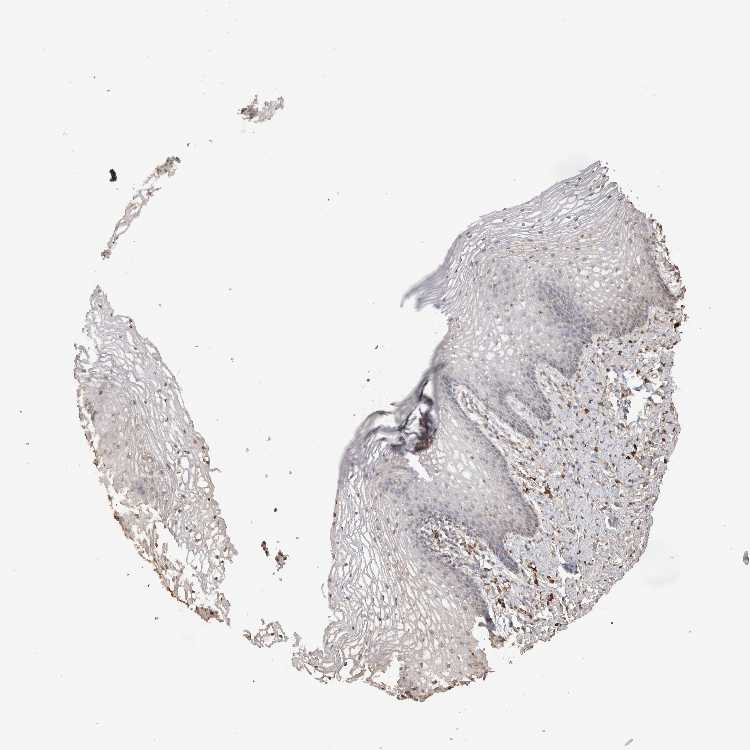

VAGINA - Antibody stainingi

Antibody staining in the annotated cell types in the current human tissue is reported as not detected, low, medium, or high, based on conventional immunohistochemistry profiling in selected tissues. This score is based on the combination of the staining intensity and fraction of stained cells.

Each image is clickable and will lead to virtual microscopy that enables deeper exploration of all samples and also displays staining intensity scores, fraction scores and subcellular localization as well as patient and tissue information for each sample.

Antibody HPA000603Antibody CAB025604

Squamous epithelial cells Not detectedLow